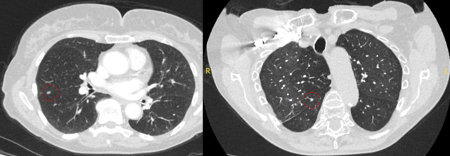

Computed tomography (CT) showing examples of malignant perifissural nodules. Note the spiculated edge of the nodules and the evident retraction of the adjacent fissure. Both resection tissue analyses confirmed adenocarcinoma of lung

From the collection of Dr George Tsaknis, MD, PhD, FRCP(London), MRQA, MAcadMEd, PGCert; used with permission